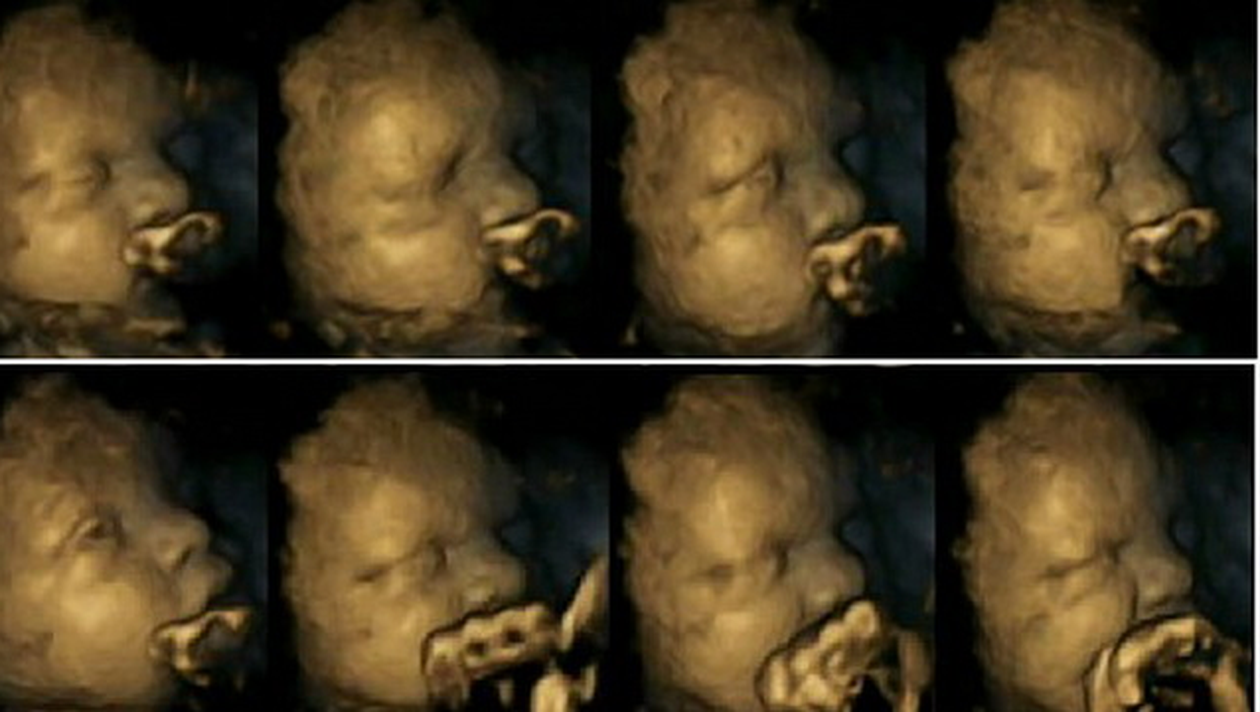

In imaginile de mai sus a fost suprins fatul unei mame care nu fumeaza. In imaginea din interiorul articolului se vede diferenta socanta cu un fat de aproximativ aceeasi varsta dar cu o mama fumatoare.

Pe langa starea de agitatie a fatului, doctorii au descoperit ca sistemul nervos central al micutilor se dezvolta mai greu daca mama nu renunta la acest viciu in timpul sarcinii.

“Ca sa tragem aceste concluzii finale trebuie sa mai efectuam cateva teste in care sa evidentiem efectele fumatului asupra stresului matern”, a spus Dr. Nadja Reissland.